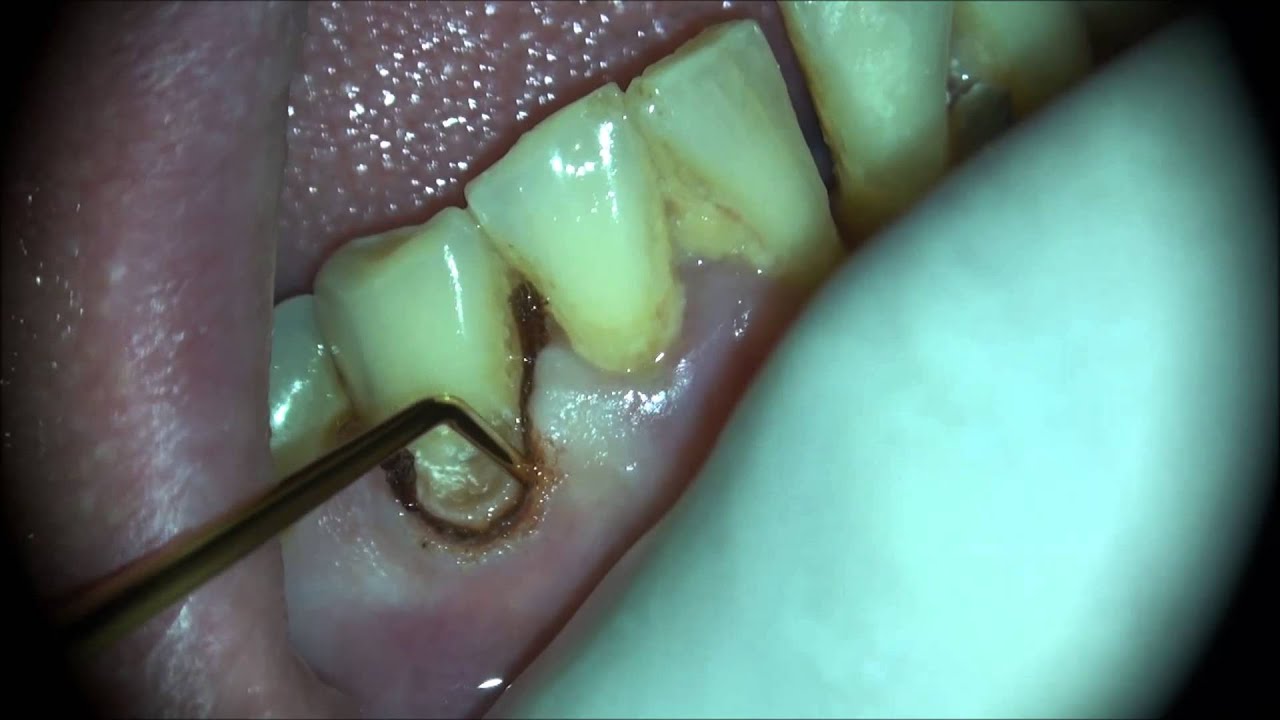

Bl5 laser gingivectomy and filling using dental microscope YouTube